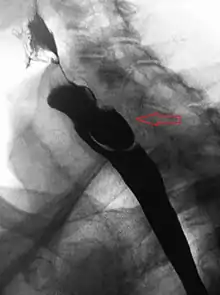

A Zenker's diverticulum, also pharyngeal pouch, is a diverticulum of the mucosa of the human pharynx, just above the cricopharyngeal muscle (i.e. above the upper sphincter of the esophagus). It is a pseudo diverticulum (not involving all layers of the esophageal wall).

More precisely, while traction and pulsion mechanisms have long been deemed the main factors promoting development of a Zenker's diverticulum, current consensus considers occlusive mechanisms to be most important: uncoordinated swallowing, impaired relaxation and spasm of the cricopharyngeus muscle lead to an increase in pressure within the distal pharynx, so that its wall herniates through the point of least resistance (known as Killian's triangle, located superior to the cricopharyngeus muscle and inferior to the thyropharyngeus muscle. Thyropharyngeus and cricopharyngeus are the superior and inferior parts of inferior constrictor muscle of pharynx respectively). The result is an outpouching of the posterior pharyngeal wall, just above the esophagus.[3]

A combination of the simple barium swallow and a thorough endoscopy will normally confirm the diverticulum.[4]